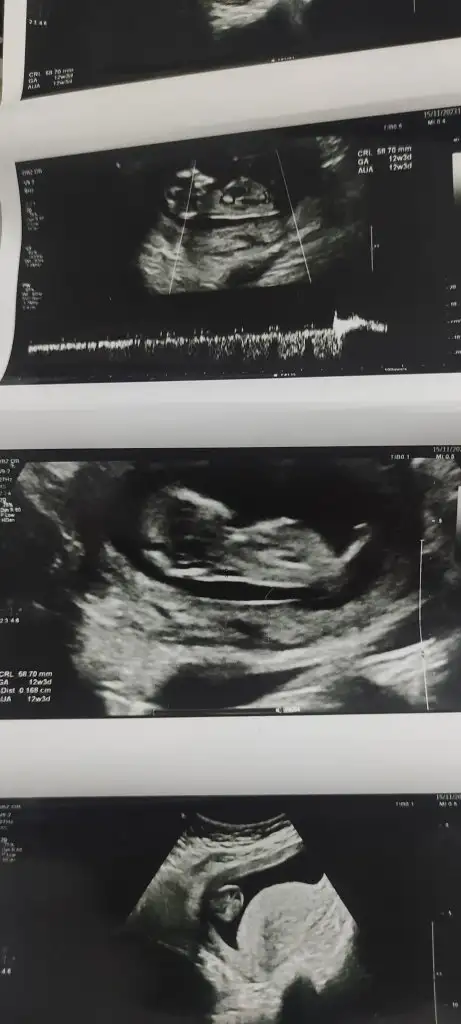

Ya benim içinde tahmin yapar mısınız? İlk resim 12 hafta ikinci ve üçüncü 6 hafta iken son fotoğrafta 14 hafta. Sizce cinsiyeti ne belli oluyor mu?